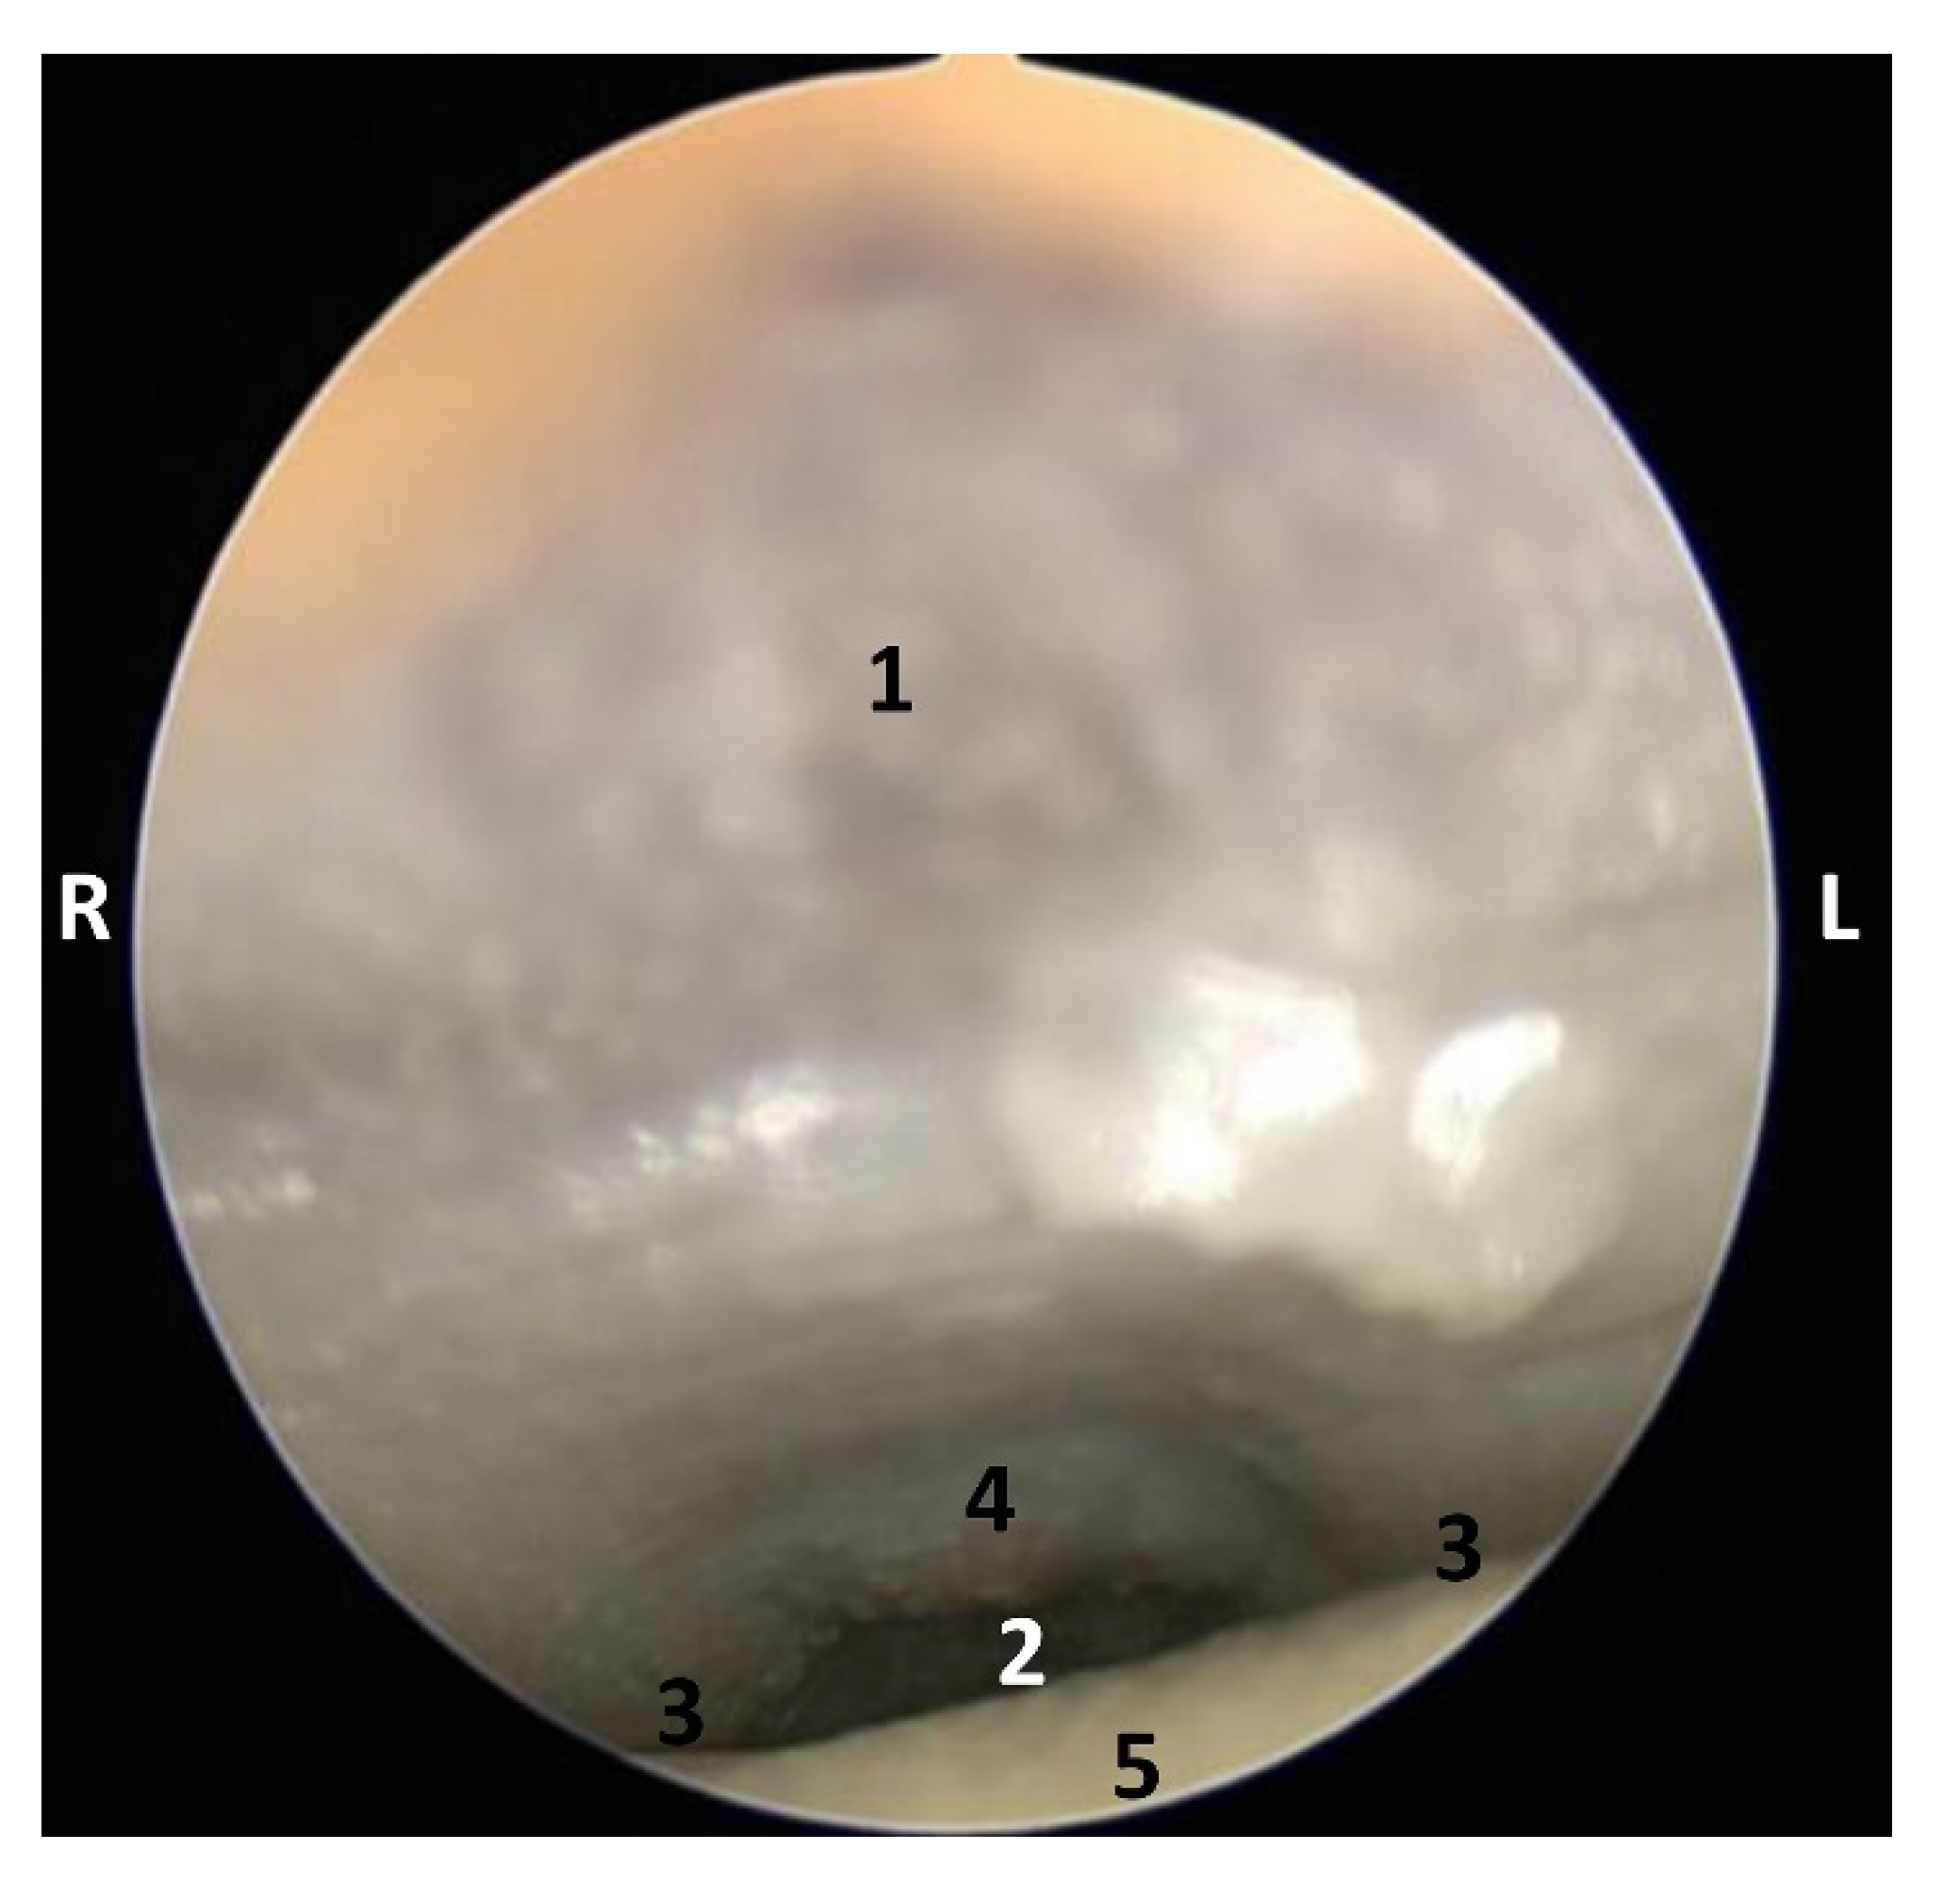

The endoscopic study began at the oropharynx, showed a tightly closed isthmus of the fauces in a young fetus, a Delphinus delphis (dde2). The endoscope could not cross this gate (Figure 16).

Figure 16.

Endoscopic image of the pharyngeal cavity: oropharynx. L (Left) R (Right). Fauces: isthmus. 3.5 months, dde2. 1, Hard palate; 2, Isthmus of the fauces; 3, Arcus palatoglossus or palatoglossus folds; 4, Soft palate; 5, Tongue: root.